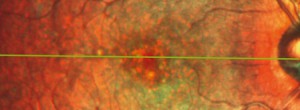

Optical Coherence Tomography Assessment of Apparent Foveal Swelling in Patients with Foveal Sparing Secondary to Geographic Atrophy.